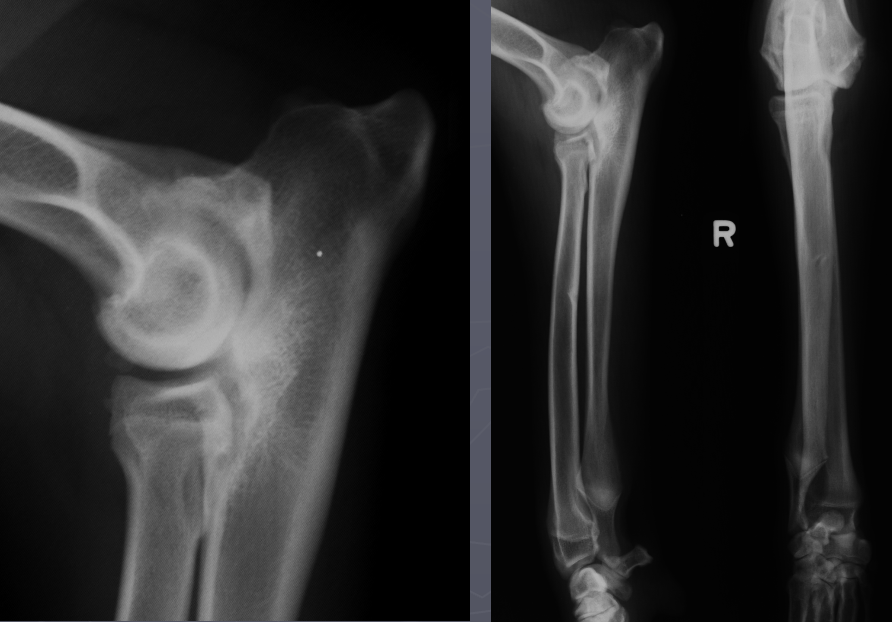

What is shown in this radiograph?

premature distal ulnar physis closure

-bowing of radius

widening of humero-ulnar joint space due to premature distal ulnar physis closure